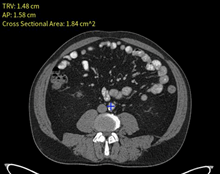

Aortic Aneurysm AI

Aortic Aneurysm Detection

Automatic Detection on CT Exams Using Deep Convolutional Neural Networks.

A. Ha, C. Fang, S. Baig, B. Do